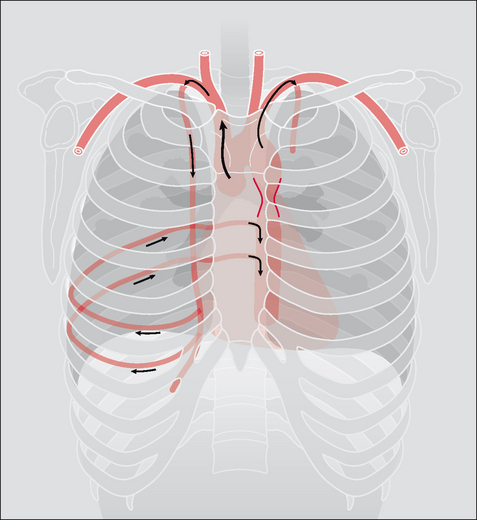

The narrowing of the aorta is shown in Fig. 31.1.

Figure 31.1 Coarctation. To show the site of the aortic narrowing at, or close to, the isthmus of the aorta. (a) Frontal CXR. (b) Lateral CXR. The aortic isthmus is the anatomical site of the junction of the arch and descending aorta.

Figure 31.2 Coarctation. The rib notching results from the anastomosis between the internal mammary arteries and the descending aorta—via the posterior intercostal arteries. The dilated posterior intercostal arteries cause the rib notching.